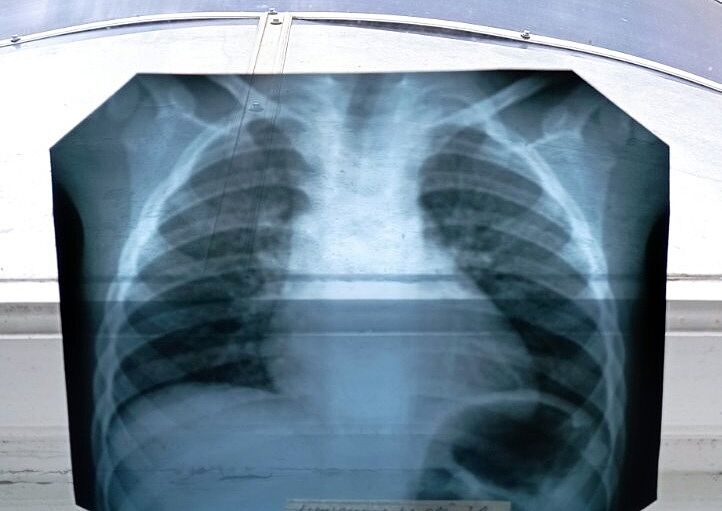

По поводу бронхитов/ пневмоний - можно сделать снимок и сходить к пульмонологу, если лечение не помогает

Я не знаю чи допомагає. Лікар сказала, що антибіотик починає діяти через 72 години. Я хвилююсь, що температура так довго

Лікар сказала такий діагноз, а в описі рентген інший лікар те ж саме написав

а рентген когда делали?

8 травня

следите сами за состояние ребенка. педиатр может просто не слышать ничего стетоскопом.

у нас после недели-двух лечения дома антибиотиками приходилось ложиться в инфекционку - так это я выбивала направление на рентген в частную клинику (потому что гос рентген не каждый день работает). ну и на современном цифровом рентгене была картина маслом(((